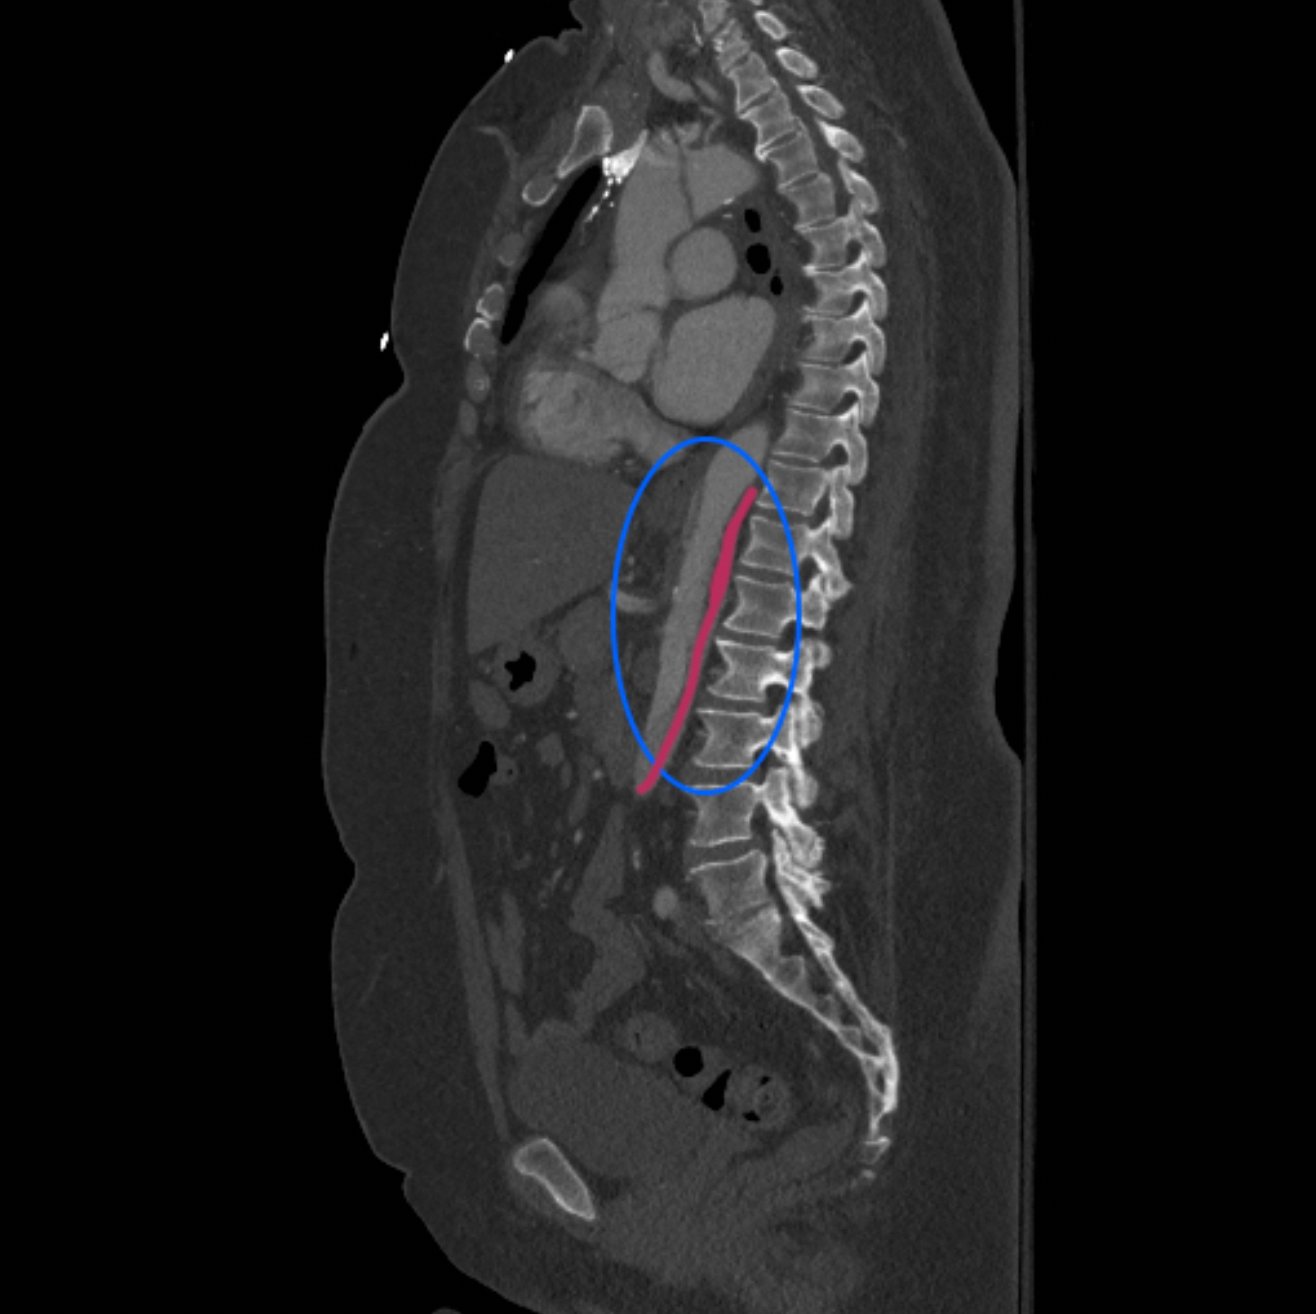

Because aortic dissection was suspected, the patient underwent urgent computed tomography (CT) angiogram of her chest, abdomen and pelvis that revealed her diagnosis.

The patient was found to have a Stanford type A dissection (see yellow arrow) with visible false lumen starting at aortic arch (see green circle). The dissection extended into the descending aorta (see blue circle) as shown by the false lumen (red highlighted area) visible on CT. The radiologist performed a reconstruction of the aorta, which showed that the left kidney was not being perfused, making the kidney not visible on the reconstruction.